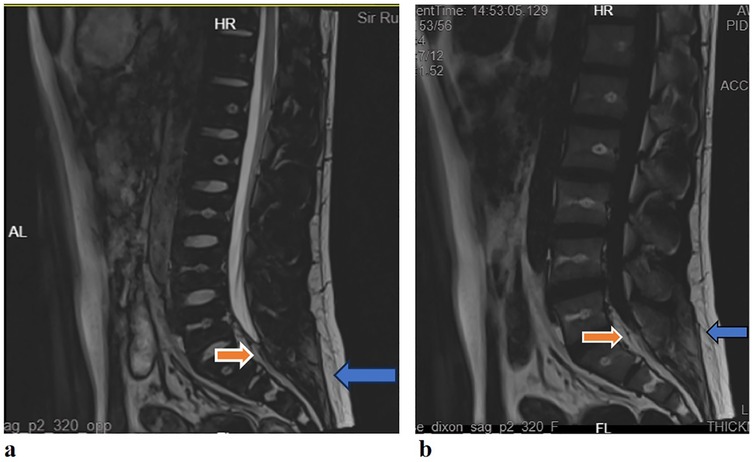

The results of the neuroelectrophysiological examinations revealed an abnormal SSR waveform in the pudendal nerve and prolonged BCR latency (Table 1 and Figure 1). The pudendal nerve SSR indicated extremely low sympathetic excitability. In addition, the patient reported a long-standing habit of holding urine. Combined with the electromyographic results, a partial injury to the pelvic nerve plexus was suspected, and treatment with mecobalamin was initiated. Subsequently, the patient developed tightness in the right pelvic floor muscles, and the symptoms gradually developed into decreased sensation in the sellar region, with frequent urination and urinary leakage. The patient returned to our hospital for inpatient treatment 3 months later (November 2024). A physical examination showed normal muscle strength and tension in all limbs; a decrease in acupuncture sensation around the anus and right saddle area; positive tenderness in the right gluteus medius, the upper middle segment of the iliotibial tract, and the piriformis muscle; and a decrease in deep pressure sensation on the right side during the anal examination. The right hamstring, rectus femoris, and quadratus lumborum muscles were tense, as were the left iliopsoas and rectus femoris muscles. There was no tension or tenderness in his other muscles. Furthermore, the patient’s bilateral knee reflexes and tendon reflexes were normal. He was negative for bilateral ankle spasms, and his bilateral Babinski signs were also negative. The patient’s visual analog scale (VAS) score was 2. An ultrasound of the urinary system indicated fullness of the prostate gland. The residual urine volume examination of the bladder indicated a residual urine volume of approximately 2 mL after urination. The patient underwent pelvic floor electrophysiological examinations again, and the results showed that the injury had progressed. In addition to the previously observed abnormal pudendal nerve SSR waveform (Figure 1) and prolonged BCR latency, there was also a prolonged SSEP latency (prolonged SSEP latency of the dorsal penile nerve) and a slightly elevated systolic potential in the patient’s right urethral sphincter (Table 1). Taken together, these electrophysiological findings suggested a broad neural injury. Combined with the patient’s abnormal BCR and SSEP, there was suspicion of a high possibility of sacral nerve injury and partial injury to the pelvic nerve plexus. Lumbar and sacral MRIs were recommended. The enhanced lumbar plexus MRI examination showed increased epidural fat at the L5/S1 level, occupying approximately 50% of the spinal canal (Figure 2). Based on his medical history, physical examinations, and imaging results, the patient was ultimately diagnosed with SEL. During hospitalization, the patient mainly received rehabilitation treatment (extracorporeal shock wave therapy, electroacupuncture, biofeedback, and transcranial magnetic stimulation). After 10 days of treatment, the patient refused to continue the treatment due to significant emotional fluctuations and was discharged.

Figure 2. (a) Lumbar sacral MRI (T2WI): the sagittal plane showed a high signal behind the L5/S1 cone in the spinal canal (red arrow), which was the same as the fat signal (blue arrow); (b) lumbar sacral MRI [T2 fluid attenuated inversion recovery (FLAIR)]: the sagittal plane showed high signal behind the L5/S1 cone in the spinal canal (red arrow), which was the same as the fat signal (blue arrow).